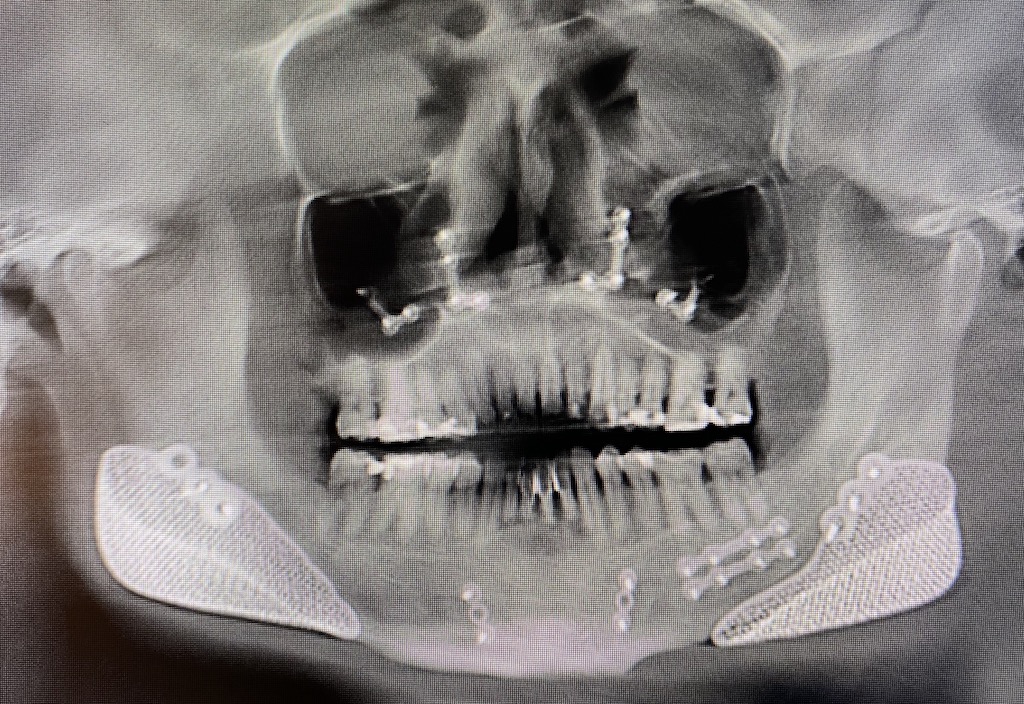

Xray showing metal plates in the upper and lower jaws after surgery Titanium Plate In Jaw Side Effects Convenience most patients will be able to resume most normal daily activities after. the toxicity of titanium implants revealed 734 results, including titanium corrosion and titanium. as with any surgical procedure, getting dental implants can pose risks. side effects can include allergic reaction to the implant, bleeding, scarring, and more. Here's a look at some rare titanium. Titanium Plate In Jaw Side Effects.